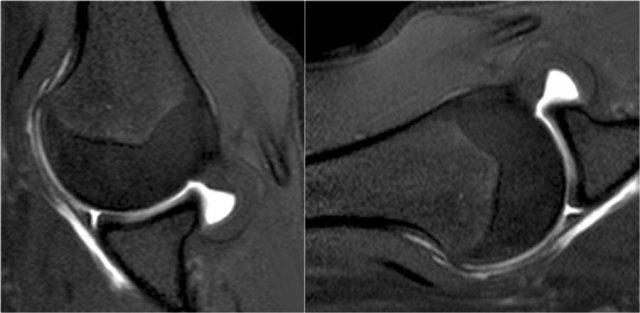

Tổn thương Bankart kèm mảnh xương là phát hiện thường gặp ở bệnh nhân trật khớp ra trước và thường được nhìn thấy trên X-quang hoặc CT.

Trên MRI khớp cản từ, việc xác định mảnh xương có thể gặp khó khăn.

Trên CT, mảnh xương ở phía trước ổ chảo dễ dàng được nhận diện (mũi tên).

Cuộn qua các hình ảnh.

Có tổn thương Bankart xương (mũi tên đỏ cong).

Đường rách lan lên trên (mũi tên đen).

Ngoài ra còn có khuyết Hill-Sachs (mũi tên đỏ).

Hình MRI khớp cản từ mặt phẳng đứng dọc cho thấy sự lan rộng lên trên của đường rách Bankart.

Đây là một bệnh nhân khác có Bankart xương được thấy trên bốn hình ảnh liên tiếp của MRI khớp cản từ ở tư thế ABER.

Lưu ý đường viền bất thường của ổ chảo phía trước và bờ trước bị avulsion (mũi tên)